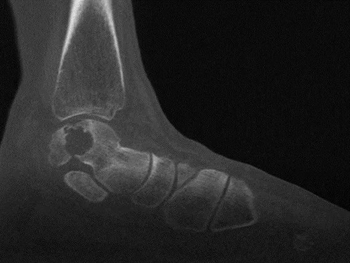

消毒铺单完毕后,武勇主任熟练地进行了胫骨V型截骨,显露关节,找到病变的区域,将事先设计好的导板贴附在距骨的病变区,按照截骨导板,精准地铲除了病变的区域,装入试模假体,对截骨的底部进行了细微地调整,再次放入试模发现贴合良好,于是将3D打印的假体置入,克氏针固定截骨端,活动踝关节,确定周围组织无撞击以及假体初始稳定性良好,透视关节对合良好,遂拧入两枚空心钉固定,逐层缝合手术结束。手术过程非常顺利,用时不到1个小时。

术后第二天查房时樊先生表示,现在疼痛明显减轻很多,没想到这么复杂的手术竟然这么顺利,术前紧锁的眉头终于舒展了。再经过两天的住院观察,拆除石膏后便可立刻开始非负重锻炼,很快就可以回家康复。